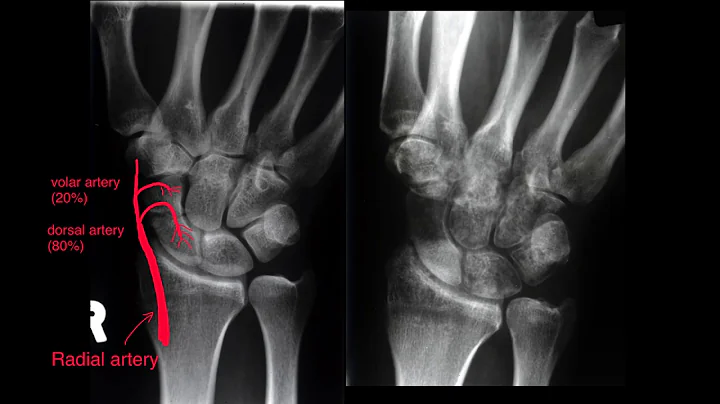

Scaphoid Fractures

Scaphoid Fractures: Diagnosis, Management, and Complications. Scaphoid fractures, a common wrist injury often resulting from a ...